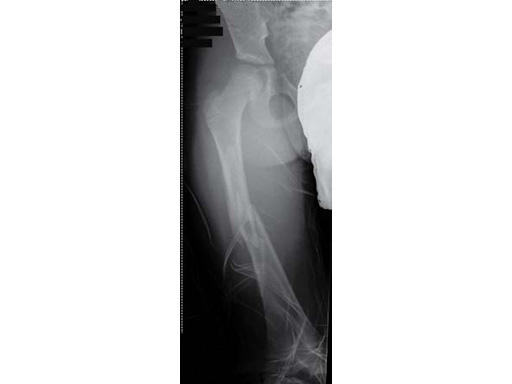

Case of a 8-year old boy with a closed lower leg fracture after football game. Control at 4 and 8 weeks after fractrure.

8-year-old boy.

Case provided by Steffen Berger and Theddy F Slongo, Bern, CH